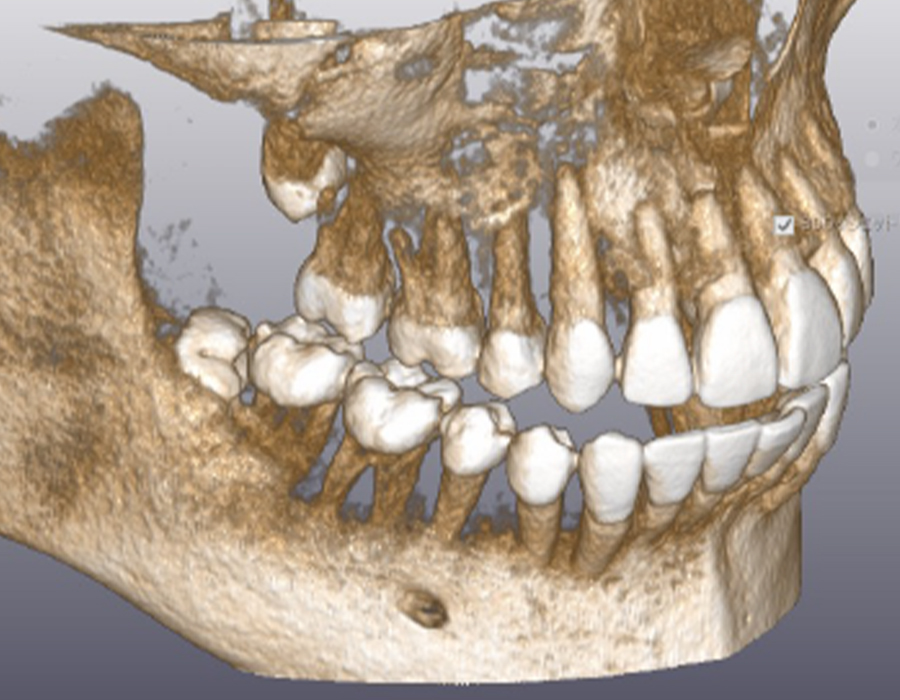

診療案内 medical information ホーム 診療案内 当院の治療のご案内 虫歯治療なるべく虫歯以外の部分を削らないようにし、患者様にも確認してもらいながら治療を進めます。もっと見る 予防歯科 (PMTC) 虫歯の早期発見のためにも当院は定期的な予防歯科をおすすめしております。もっと見る 小児歯科小児歯科は、成長発達期にある子どもの歯および顎や口を管理し、発育を助けるための医療です。もっと見る セレック即日で治療を行います。天然歯に近い美しいセラミックで、きれいに治療します。もっと見る 審美歯科虫歯治療をはじめ、気になっている箇所を美しく治療します。もっと見る ホワイトニング歯を削らずにスピーディーに歯を白くします。治療回数は3回となっております。もっと見る 歯周病治療歯茎が下がってきたり、口臭が気になる方に検査を受けていただき、最適な治療を行います。もっと見る インプラントインプラントをいれたその日からご飯が食べられます。入れ歯が合わない方もご相談ください。もっと見る デンチャー(入れ歯)60年の伝統に裏打ちされた治療を行います。もっと見る 訪問診療ご自宅や、施設まで診療に伺います。もっと見る 根管治療(歯の根の治療)再発がなるべく起こらない治療を目指しています。もっと見る かぶせ物やつめものの再発を少なくするために大切な身体の一部である歯を、可能な限り残す治療に取り組みます。もっと見る 親知らず抜歯大学病院に勤務しているDrによる親知らず抜歯を行っております。もっと見る 歯の移植歯がなくなった場合、インプラント、ブリッジ、入れ歯以外に、第4の選択肢として、歯の再植というものがあるのはご存じですか?もっと見る 有病者歯科ご病気のある方、基礎疾患、既往のある方の歯科治療。もっと見る 子供や大人の歯と口のケガ(外傷)当院では、近在教育機関の校医を行っており、長年歯や口のケガをした方の対応をしております。もっと見る マタニティ歯科これから妊娠をお考えや、妊娠中の方で、お口の中のトラブルひいては胎児への影響を少なくするために努めていきます。もっと見る セラミック、かぶせもの、詰め物の治療機能性にも審美性にもこだわる、調和のとれた審美治療を行います。もっと見る 矯正治療 歯並び 不正咬合部分矯正、ワイヤー矯正、マウスピース矯正、マウスピース矯正とワイヤー矯正を組み合わせて行うコンビネーション矯正治療が可能です。もっと見る 鎮静による治療法、当院が行っている痛みの少ない治療への取り組み、歯科集中治療のご提案無痛治療とまではいかないまでも極力痛みを少なくした状態で歯科治療を目指す方法として鎮静法があります。もっと見る 顎関節治療、歯ぎしり、噛みしめの治療顎関節症の原因は、様々な因子が関係しているといわれております。当院は大学病院口腔外科にて幅広く研鑽をつんだ副院長が、顎関節治療を行っております。もっと見る